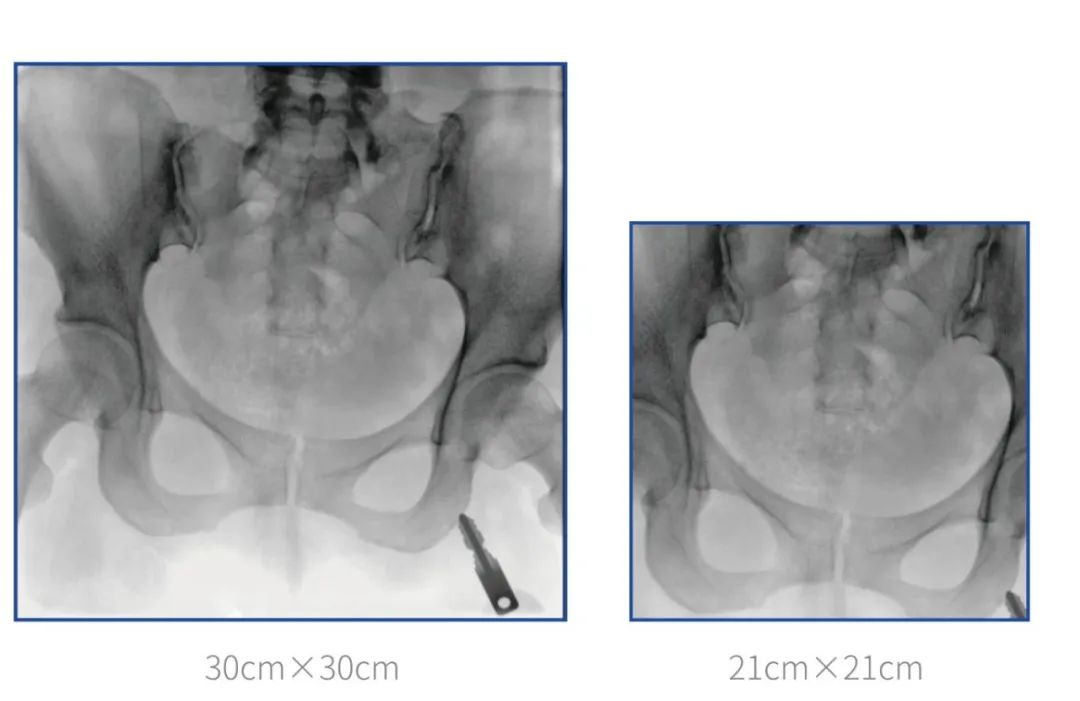

大尺寸平板C形臂? 提供更多圖像細節(jié)

普愛醫(yī)療堅持自主研發(fā)、持續(xù)創(chuàng)新,從臨床需求出發(fā),推出了大視野,能夠呈現(xiàn)更多圖像細節(jié)的大平板一體式C形臂。大平板一體式C形臂配置30cm×30cm平板探測器,對于諸如骨盆雙側(cè)骨折類型手術(shù)或骨盆后環(huán)內(nèi)固定術(shù)具有應(yīng)用優(yōu)勢,一次曝光可獲取全部骨折部位影像,可簡化曝光流程,提高手術(shù)效率!